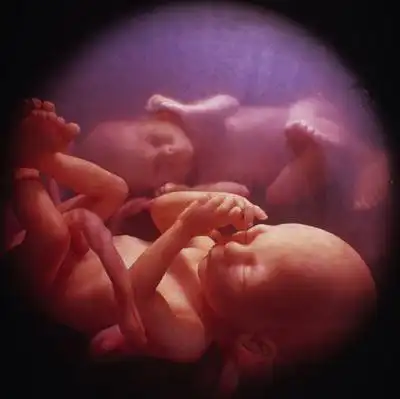

Сегодня жизнь близнецов начинают "контролировать" еще за долго до родов. И ученые пришли к удивительному выводу - близняшки общаются друг с другом еще в утробе матери!..

А вот этот - "Диалог"...